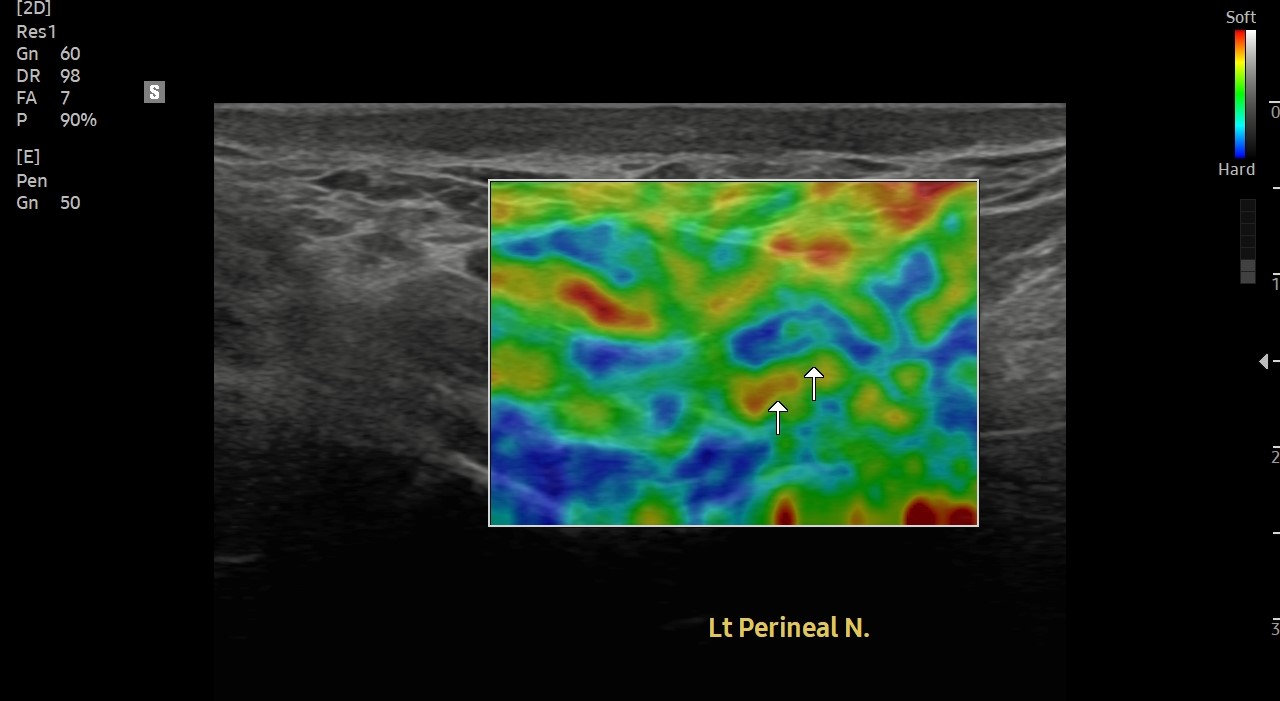

[치료 전]

[치료 후]

- 치료횟수 : 40 회